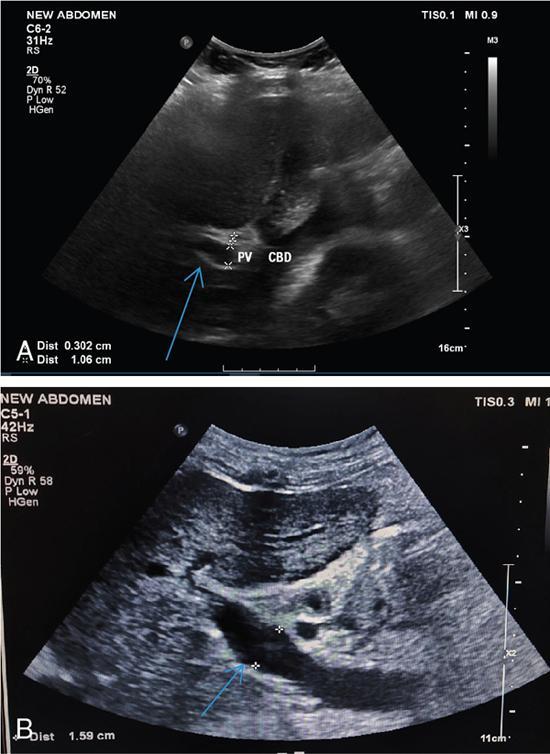

Shrinivas B. Desai, Ritu K. Kashikar, Aman Snehil, Ajay Jhaveri Cirrhosis is a late stage of irreversible scarring of the liver causing abnormality in liver structure and function. Multiple conditions and factors can cause repeated liver damage and scarring ultimately leading to cirrhosis. The most feared complication of liver cirrhosis is the development of hepatocellular carcinoma (HCC). Portal hypertension (PHT) is seen with a variety of conditions but cirrhosis happens to the most important cause. Imaging plays a vital role in noninvasive diagnosis and treatment planning of both cirrhosis and PHT. Liver imaging reporting and data system (LI-RADS) is a standardized reporting system assigning an observation risk of representing HCC. This chapter focuses on discussing aetiologies and imaging of PHT with a lucid review of L1-RADS 2018 version. The portal blood circulation is a unique circulatory circuit as it connects two capillary beds between the liver parenchyma at one end and the gastrointestinal tract and splenic parenchyma at the other end. The portal system ramifies in the liver and ultimately ends in the hepatic sinusoids from where the blood ultimately drains into the inferior vena cava (IVC). The portal vein (PV) originates from the capillary beds in the stomach, intestine and the spleen. The main PV is formed behind the neck of the pancreas by the confluence of the superior mesenteric vein (SMV) and splenic vein. It continues to the porta hepatis where it bifurcates into the left and right branches as it carries nutrient rich but oxygen poor blood to the liver (Fig. 9.9.1). The PV makes up for 75%–80% of the liver’s blood supply while the hepatic artery which arises from the celiac trunk makes up for the remaining 25%. A pathological increase in the portal venous pressure is referred to as PHT. PHT is most often a sequel of chronic parenchymal liver disease and leads to major life-threatening complications due to bleeding from the collateral circulation (most commonly oesophageal varices). Direct measurement of portal pressure (PP) is invasive and often not feasible in most patients and thus imaging plays an important role in the diagnosis of PHT and its complications. The normal portal venous pressure ranges between 5 and 10 mmHg, which is the equivalent of 7–14 cm H2O. The normal hepatic venous pressure gradient (HVPG) is the pressure gradient between the PV and the IVC, is typically 1–5 mmHg. Presence of PHT is indicated by a wedged hepatic venous pressure of more than 5 mmHg. Other definitions include a splenic pressure of more than 15 mmHg or an intraoperative PP of greater than 30 cm H2O. The complications of PHT are seen when HVPG is greater than 10 mmHg and hence this value defines clinically significant PHT. Variceal bleeding is seen with a pressure greater than 12 mmHg. In ideal conditions, the portal circuit is a high flow, low resistance circuit as it has to allow substantial flow rates of 700–1000 mL/min to the hepatic parenchyma from the gastrointestinal tract. Anatomical changes in the organization of the hepatic lobule can result in rise in the portal resistance. These can occur in the form of collagen deposition in the space of Disse, fibrotic scars formed due to regenerative nodule (RN) formation, loss of normal elasticity of the endothelium and distal venous thrombosis. Changes in splanchnic haemodynamics due to factors that increase splanchnic blood flow and increase in intrahepatic vascular resistance due to transformation of stellate cells into myofibroblasts also contribute to the increase in PP gradient. In Western countries, alcoholic cirrhosis and viral cirrhosis are the leading causes of PHT and oesophageal varices. The viral causes form majority of cases leading to cirrhosis and PHT in the Far East and Middle Eastern countries while Schistosomiasis remains an important cause in the African countries. Worldwide, nonalcoholic steatohepatitis (NASH) and hepatitis C are the emerging causes of chronic liver disease (CLD) and PHT. PHT can be classified as cirrhotic and noncirrhotic depending on whether it is associated with cirrhosis or not. This distinction is important as noncirrhotic causes like PV thrombosis are at high risk of development of bleeding but tend to have a better chance of surviving a variceal bleed than a patient with decompensated alcoholic cirrhosis due to preserved hepatic synthetic functions in the former. PHT can also be classified on the basis of the location of the pathology into prehepatic, hepatic and posthepatic causes. Hepatic causes can further be divided into presinusoidal, sinusoidal and postsinusoidal. The causes of portal hypertension have been denoted in Table 9.9.1. The direct measurement of the PP by measuring the HVPG is invasive, expensive not readily available in all patients. Thus, imaging plays an important role in the diagnosis of PHT. Various modalities are used for the imaging diagnosis of PHT. Ultrasonography (USG) and Doppler evaluation have the advantage of being inexpensive, readily available and bedside modality (Table 9.9.2). The role of ultrasound and Doppler in imaging of PHT is to: Grey scale imaging is useful in evaluating the splenoportal anatomy. The evaluation should begin with the liver morphology. Signs of cirrhosis like nodularity of the liver surface with relative atrophy of the right lobe and prominence of the left lobe and caudate should be looked for. Hepatic echotexture appears coarse and more echogenic (Table 9.9.3). Increase in portal venous diameter is a sign of PHT (Fig. 9.9.2). Portal venous diameter of more than 13 or 15 mm has low sensitivity for diagnosing PHT of only 40%–12.5%, respectively. Absolute measurement of the portal diameter as a sign of PHT is also fallacious as in presence of collateral circulation or hepatofugal flow; there may actually be a decrease in the PV diameter. Therefore, a more accurate sign is respiratory variation of PV diameter. An increase in PV diameter of less than 20% with deep inspiration has been reported to indicate PHT with a sensitivity of 80% and specificity of 100%. This has been reported to be an accurate indicator of cirrhosis. Hepatic vein straightness, uniformity of vein wall echogenicity and visualization of at least 1 cm segment of the hepatic vein are the parameters used for evaluation. Splenomegaly is defined as bipolar splenic diameter of greater than 12 cm or largest splenic cross-sectional area passing through the hilum of greater than 45 cm2, and occurs secondary to PHT (Fig. 9.9.3). A total of 65%–80% patients with cirrhosis have splenomegaly on ultrasound. Patients with cirrhosis due to viral hepatitis and primary biliary cirrhosis show splenomegaly more frequently than those with alcoholic cirrhosis. This is an accurate sign of PHT. USG is extremely sensitive with respect to detecting subclinical ascites. Perihepatic space is the most usual site of visualization of minimal ascites. In normal subjects, this ratio is approximately 0.07 and a value above 0.1 suggests the diagnosis of PHT with a 95% sensitivity and specificity. The normal spectral waveform of the hepatic artery is a low resistance flow pattern with forward flow in diastole and a resistivity index in the range of 0.5–0.7. In PHT, the resistivity index of the hepatic artery increases with high resistance flow pattern due to increased peripheral vascular resistance. Resistance index (RI) > 0.78 in the intrahepatic branches of the hepatic artery has been reported to have a sensitivity of 50% and a specificity of 100% for the detection of PHT (Fig. 9.9.11). Pulsatility index (PI) > 1.05 suggests severe PHT with a sensitivity of 86% and specificity of 88% (Fig. 9.9.11). Patency of hepatic veins should be evaluated to rule out Budd–Chiari syndrome as a cause of PHT. The normal hepatic venous waveform (HVW) reflects right atrial activity and this results in a triphasic waveform with one positive and two negative waves. In PHT, this waveform becomes monophasic or biphasic. A monophasic HVW has a sensitivity and specificity of 74% and 95%, respectively, in the diagnosis of severe PHT (Fig. 9.9.12). Dilatation of the splanchnic veins – the SMV and the splenic vein – more than 11 mm are suggestive of PHT with a sensitivity and specificity of 72% and 100%, respectively. A reduction in the respiratory variation of the splenic vein and SMV to less than 40% had a sensitivity and specificity of 79.7% and 100%, respectively, for the diagnosis of PHT (Fig. 9.9.13). The splenic artery reveals an increase in the resistivity index and an RI of >0.63 and a PI of >1 have a sensitivity and specificity of 84.6% and 70.4% for the diagnosis of PHT. Presence of portosystemic collaterals like patent paraumbilical vein, dilated left gastric and short gastric veins are 100% specific sign for PHT (Figs. 9.9.14–9.9.16). Recanalization of the paraumbilical vein, known as the Cruveilhier–Baumgarten syndrome is observed in 43% of patients with PHT, and this is the easiest collateral to assess during the US examination. Various portosystemic collaterals that occur in PHT have been discussed in details in subsection on CT findings in PHT. No Doppler parameter is considered reliable enough to measure PP with sufficient accuracy for use in clinical practice. Oesophageal varices are often present in patients with portosystemic collaterals. Appearance or increase in number of collaterals along with splenomegaly has a high association with variceal formation and growth. USG helps in diagnosis of prehepatic causes like portal stenosis or thrombosis by demonstrating the patency and morphology of the splenoportal system. Arteriovenous fistulae and tumours causing vascular thrombosis as aetiology can be readily detected. USG helps in diagnosis of features of cirrhosis and thus helps differentiate noncirrhotic causes of PHT. USG allows diagnosis of fatty liver disease, which is an emerging cause of cirrhosis. Among the posthepatic causes, USG aids in establishing the diagnosis of Budd–Chiari syndrome by demonstrating the patency and morphology of the IVC and hepatic veins. Owing to the inability of CT to detect flow direction, portal flow rates or pressure gradients, CT is not the primary modality in diagnosis of PHT. Similar to USG dilatation of portosystemic system is a feature of PHT (Fig. 9.9.17). Changes in cirrhosis if present can be seen in the form of surface nodularity, nodules and fibrous septae. CT plays an important role in diagnosis of portal venous thrombosis and evaluating its extent. An acute thrombus is seen as a hypodense filling defect in the vessel causing distension of the venous lumen. Surrounding fat stranding can be seen. A chronic thrombus appears as an eccentric filling defect usually along the wall and is often associated with decrease in vessel diameter. Calcification may be seen in chronic thrombi. Multidetector computed tomography (MDCT) is a useful tool to evaluate portosystemic collateral circulation and recognize complications of PHT. 3D angiography can help understand portal venous and complex variceal anatomy and plan treatment. The various portosystemic collaterals are discussed below. They can be classified into those draining into superior vena cava (SVC) and those draining into the IVC. Magnetic resonance imaging (MRI) is a noninvasive modality used in the evaluation of PHT without the use of ionising radiation. It provides evaluation of parenchymal abnormalities, collaterals and characterization of tumours (Fig. 9.9.28). Spin echo sequences allow characterization of liver masses and liver parenchyma. Loss of flow void allows for detection of thrombosis. Time-of-flight (TOF) angiography is useful in assessing the portal venous system and allows for successful detection of PV thrombosis. The disadvantages of TOF are motion artefacts caused by breathing, long acquisition times and incomplete coverage of the portal venous system. Novel imaging techniques include phase contrast, T1 mapping and magnetic resonance elastography (MRE). The advantage of phase contrast over TOF imaging is that phase contrast imaging acquires information regarding the flow direction in addition to the information regarding the flow velocity. On-phase contrast images signal within vessel is hyperintense when flow is cranial and hypointense when flow is caudal. Look-Locker imaging technique using gradient echo (GRE) MRI sequences with inversion recovery pulse is used to quantify fibrosis by measuring precontrast T1 relaxation times. Interventions in PHT can be aimed at diagnosis or more commonly at management of complications of PHT. HVPG measurement, which is the gold standard for the diagnosis of PHT, can be achieved through cannulation of the PV. Transjugular hepatic biopsy is another diagnostic invasive technique that also allows indirect measurement of PP. Disadvantages include deterioration of hepatic function caused by diversion of portal venous blood flow and shunt dysfunction. TIPSS is contraindicated in patients with congestive heart failure, severe pulmonary hypertension, severe tricuspid regurgitation and hepatic failure. In this technique, a catheter is advanced from the femoral vein into the outlet of the gastrorenal, usually in the region of the left renal vein. The shunt is then occluded with a balloon and sclerosant is injected retrograde to occlude the gastric varices. Histological development of RNs surrounded by fibrous septae in response to chronic liver injury, progressing PHT and end-stage liver disease is termed as cirrhosis. Although initially considered an end-stage phenomenon in CLD, recent evidence suggests that the histological fibrosis can be reversible in early stages with the initiation of specific therapies, for example, in viral cirrhosis with the initiation of antiviral therapy. The one-year mortality rate in cirrhosis varies widely from 1% to 57% depending on the occurrence of complications. Cirrhosis can have a wide variety of causes ranging from congenital to acquired and infectious to noninfectious. It is also a major aetiologic risk factor for the development of HCC. Imaging plays an important role in aetiologic diagnosis of this diverse entity as well as in the diagnosis and management of its complication and surveillance for oncological transformation.

Grey scale imaging

1. Portal vein diameter